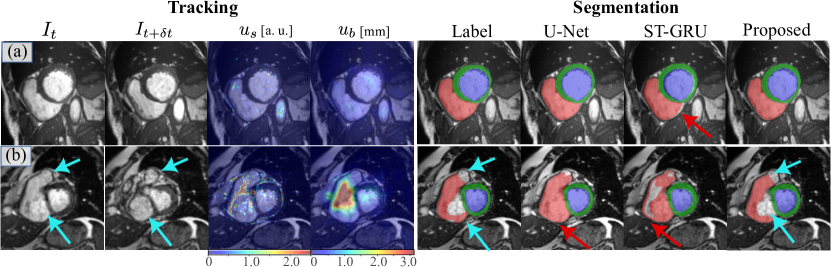

Refer to caption

Figure 3: Qualitative results of tracking uncertainty and segmentation. The left panel shows the tracking uncertainty ubsubscript𝑢𝑏u_{b} and ussubscript𝑢𝑠u_{s} between Itsubscript𝐼𝑡I_{t} and It+δtsubscript𝐼𝑡𝛿𝑡I_{t+\delta t}. The right panel shows the segmentation labels and predictions. In case (b), the atrium and valve (cyan arrows) coexist with RV, and should not be included (c.f. the anatomy in Fig. 1).

In Fig. 3, we show some qualitative results of the loss-of-tracking detection and the predicted segmentation maps. In case (a), the right ventricle preserves its shape from Itsubscript𝐼𝑡I_{t} to It+δtsubscript𝐼𝑡𝛿𝑡I_{t+\delta t}, and the detected loss-of-tracking ussubscript𝑢𝑠u_{s} and ubsubscript𝑢𝑏u_{b} stays on a relatively low level. On such images, all methods can correctly predict the RV segmentation map. However, the ST-GRU prediction still has a small deviation from the ground truth on ventricular borders (red arrow). We conjecture that ST-GRU suffers from imperfect motion tracking here. In case (b), we show a basal slice with strong interplanar motion on which the RV and valves can hardly be distinguished from the single image Itsubscript𝐼𝑡I_{t}. The detected loss-of-tracking ubsubscript𝑢𝑏u_{b} highlights the area that cannot be tracked from Itsubscript𝐼𝑡I_{t} to It+δtsubscript𝐼𝑡𝛿𝑡I_{t+\delta t}, mainly in RVOT. The MSE pattern ussubscript𝑢𝑠u_{s} approximately delineates the separation between the valves and the RV. In this slice, the U-Net has difficulty in predicting RV segmentation in a single image Itsubscript𝐼𝑡I_{t}, but the proposed method can successfully predict the RV border with loss-of-tracking taken into account. In this case, taking segmentation consistency for granted like ST-GRU can harm the segmentation accuracy.